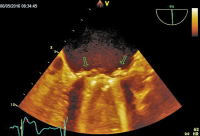

Vollbildansicht

TEE

Abbildung 4: Deutliche Regression der Vegetationen nach 4-wöchiger Antibiose